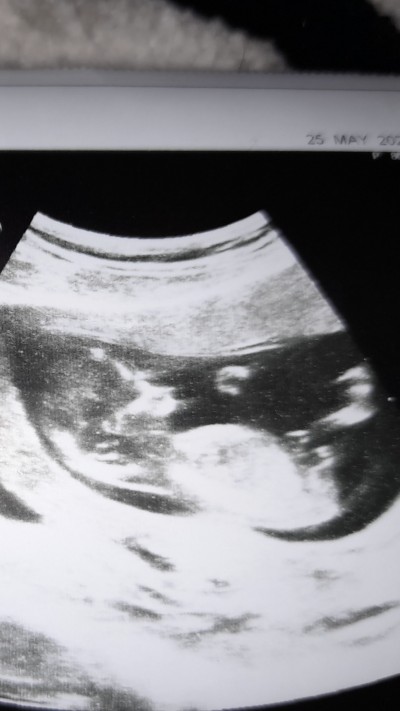

image

Minnoş bi kız zannımca çünkü erkek bebekler kendıni cok cabuk bellı edıyorlar benm oglandan biliyorum

Birinci foto sekız ıkıncı foto 12 haftalık ne kadar bellı elı kolı bacagı uzuvları